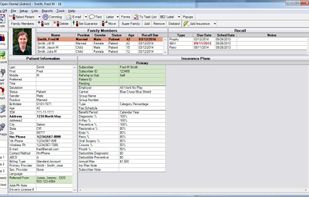

Clear.Dental is described as 'Open Source Dental Practice and Treatment Planning Software' and is an app. There are four alternatives to Clear.Dental for a variety of platforms, including Windows, Web-based, Android, iPhone and iPad apps. The best Clear.Dental alternative is Open Dental, which is both free and Open Source. Other great apps like Clear.Dental are Dentrix, Dentem and 365Apex.